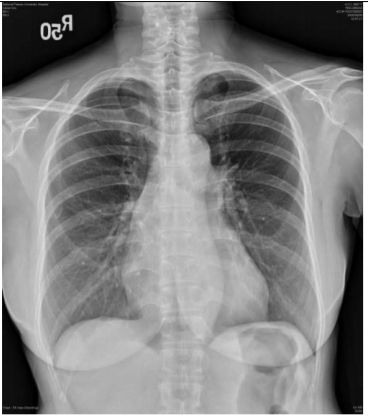

5. 病人男性59歲於午夜24時,突因胸悶並有牙床緊疼,乃直往急診部求診,時病人之T/P/R = 35.1/51/18, BP 137/74 mmHg; 理學檢查,未見任何異常。病史追尋,本病人曾經醫師確定高血壓、高脂血、糖尿病及攝護腺肥大,唯僅只服用Bisoprolol 2.5 mg/day。經緊急檢查:其心電圖及胸部X光顯示如圖:生化檢查: CK,96 U/L;CK-MB,20 U/L;TnI <0.0012 ng/ml;Sugar 252 mg/dL; Na,137 mmol/L; K, 3.7 mmol/L; TG,182 mg/dL and Total cholesterol, 222 mg/dL ; 血液檢查: Hb,13.9 g/dl; Platelet, 203 K/uL; WBC,9.45 K/uL; Cre,1.3 mg/dL 請問本病人最可能的急診診斷是:

(A) Printzmetal's angina (B) Aortic dissection (C) Acute anterior myocardial infarction (D) Hypertension (E) Acute periodontitis disease